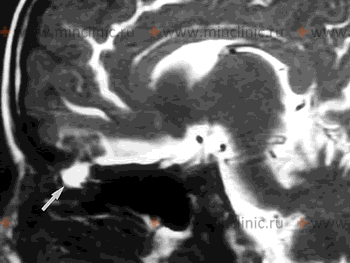

Источник назальной спонтанной ликвореи на МРТ головного мозга с контрастированием (показан белой стрелкой).